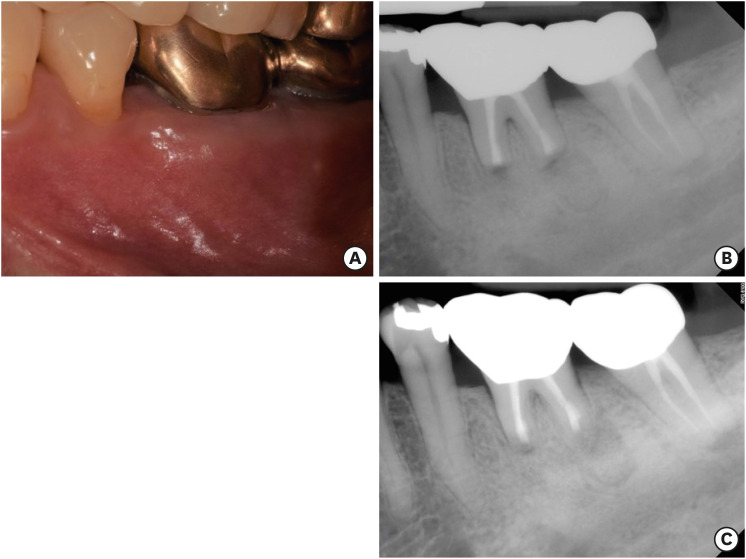

A 49 years old woman was referred from the department of periodontology due to the presence of a sinus tract on tooth #36 (Figure 1A). She did not report any discomfort associated with the tooth. The medical history was non-contributory. However, periapical radiographs with gutta-percha tracing revealed periapical radiolucent lesions associated with both mesial and distal roots of tooth #36, and the origin of the sinus tract was the distal root of tooth #36 (Figure 1B). Periodontal probing depths were unremarkable. In her dental history, she reported that tooth #36 was endodontically treated 2 years previously. Apical lesions were confirmed by CBCT images (Alphrad 3030, Asahi Roentgen Ind Ltd., Kyoto, Japan). Based on the history and clinical and radiographic examination, a diagnosis of a previous root canal treatment with chronic apical abscess was established. A decision to perform endodontic microsurgery on both mesial and distal roots of tooth #36 was made. The patient was offered all treatment options; she opted for endodontic microsurgery. Written consent was obtained. The exact localization of the apex of the 2 roots was expected to be difficult due to the presence of thick buccal cortical bone, especially close to the tip of the distal root and the inter-radicular area. Further, substantial loss of buccal cortical plate was anticipated with the traditional osteotomy technique using round burs. Therefore, cortical window access using a surgical template was planned.

Figure 1

(A) The clinical image of tooth #36 with the sinus tract on buccal gingiva (yellow arrow). (B) The initial periapical radiograph of tooth #36 showing periapical lesions and gutta percha tracing revealing the origin of the sinus tract was the distal root of tooth #36.

Figure 1 (A) The clinical image of tooth #36 with the sinus tract on buccal gingiva (yellow arrow). (B) The initial periapical radiograph of tooth #36 showing periapical lesions and gutta percha tracing revealing the origin of the sinus tract was the distal root of tooth #36.